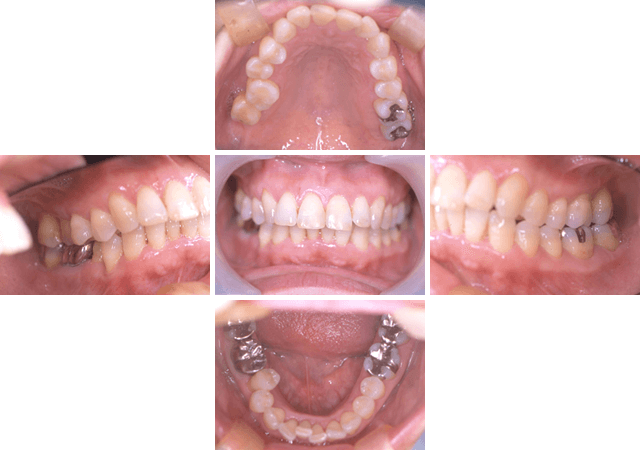

40代 女性

エムドゲインを使用した歯周治療

| 主な症状 | 歯が浮いた感じがする。 |

| 口腔内の状況 | 歯頸部にプラークが沈着しており、縁下歯石も全体的に沈着。臼歯部に発赤腫脹もみられる。中等度から重度の歯周炎。 |